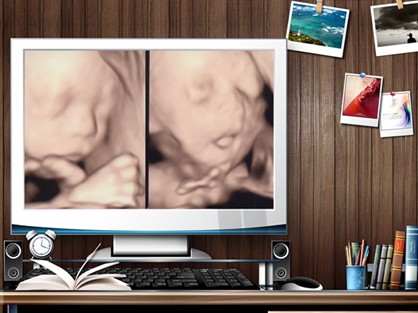

通过四维彩超,不再是仅仅能感觉宝宝的呼吸和运动,而是可以亲眼目睹他们的一举一动和乖巧的面容。四维彩超更能多方位、多角度地观察宫内胎儿的生长发育情况,为早期诊断胎儿先天性体表畸形和先天性心脏疾病提供准确的科学依据。

杭州玛莉亚妇产医院的产科四维彩超采用的是家庭影院输出模式,家属也可以在液晶屏幕上看到孕妇四维检查的全程动态情况,受到许多孕妇朋友及家属的欢迎。

四维彩超能清楚直观地显示胎儿面部情况及其相互关系,尤其是能够动态、多角度地观察宫内胎儿的颜面部、肢体的发育情况,甚至可以动态地观察到胎儿在母体里的状态,看到宝宝打哈欠、揉眼睛等可爱的动作。

深居“宫”中的小宝贝第一次伸出小脚来探测胎盘、玩弄脐带;第一次津津有味地吞咽羊水;第一次翻来覆去在妈妈肚子里发脾气……杭州玛莉亚妇产医院四维彩超把这些真善美记录下来,让准妈妈体会生命蕞初的感动。

当准爸妈透过四维彩超看到腹中胎宝宝时,回想起怀孕时点点滴滴,一切辛苦都转瞬即逝,一切都是值得的。本来有些枯燥无味的孕育生活立刻充满了无限乐趣和魅力,只是一个小小的屏幕却能清晰直观地将胎宝宝的一举一动展露无遗。